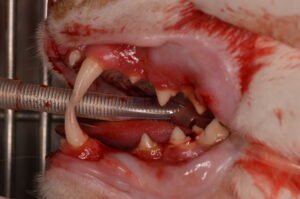

口内炎の治療のために全抜歯を行った猫ちゃんの紹介をします。

3歳のmixの男の子です🐱 口の痛みを主訴に来院されました。

ドライフードは口が痛いため食べられず、液状のおやつを食べていました。

見た目でも、口全体の粘膜が炎症によって赤くなっているのが分かります。

全身麻酔下ですべての歯を抜歯しました。

↑手術前の写真

抜歯を行ってから2週間後はまだ赤みはありますが、手術前よりも赤みの程度が引いていました。